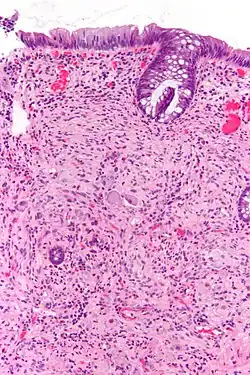

Pathology

Pathologically, ganglioneuromas are composed of ganglion cells, Schwann cells and fibrous tissue.[6] Ganglioneuromas are solid, firm tumours that typically are white when seen with the naked eye.